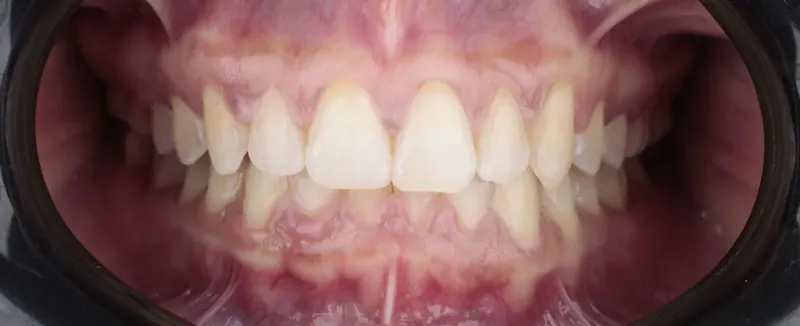

Brackets y diseño de sonrisa con flujo digital. Función y estética con mínima invasión.

- “Ortodoncia, prótesis y diseño de sonrisa con tecnología digital 3D.”